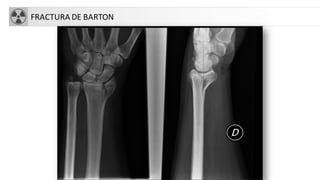

• Otras FX: Smith, Barton, Hutchinson…

FRACTURA DE BARTON